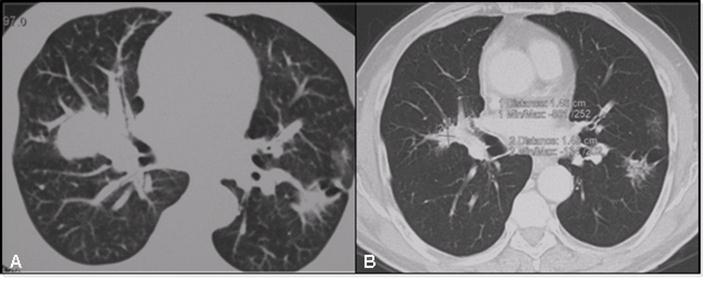

On this evidence, the patient underwent a first line platinum-based chemo (platinum-pemetrexed) but a slight disease progression was documented subsequent to 4 cycles of treatment. For that reason the patient was then treated with Erlotinib 150 mg/die. After 6 months of treatment the EGFR mutated lesion displayed a volume reduction of more than 50%; the controlateral nodule showed a less but still significant (15 %) reduction in both diameter and density (Fig.2). Overall CT scans were performed as a control after therapies and objective response was evaluated according to RECIST criteria7.

Figure 2

Evolution of tumor lesions after 6 months therapy with erlotinib as documented by CT scan. Panel A: thoracic CT scan, after chemotherapy. Panel B: thoracic CT scan after 6 months of therapy with erlotinib, 150 mg/die.